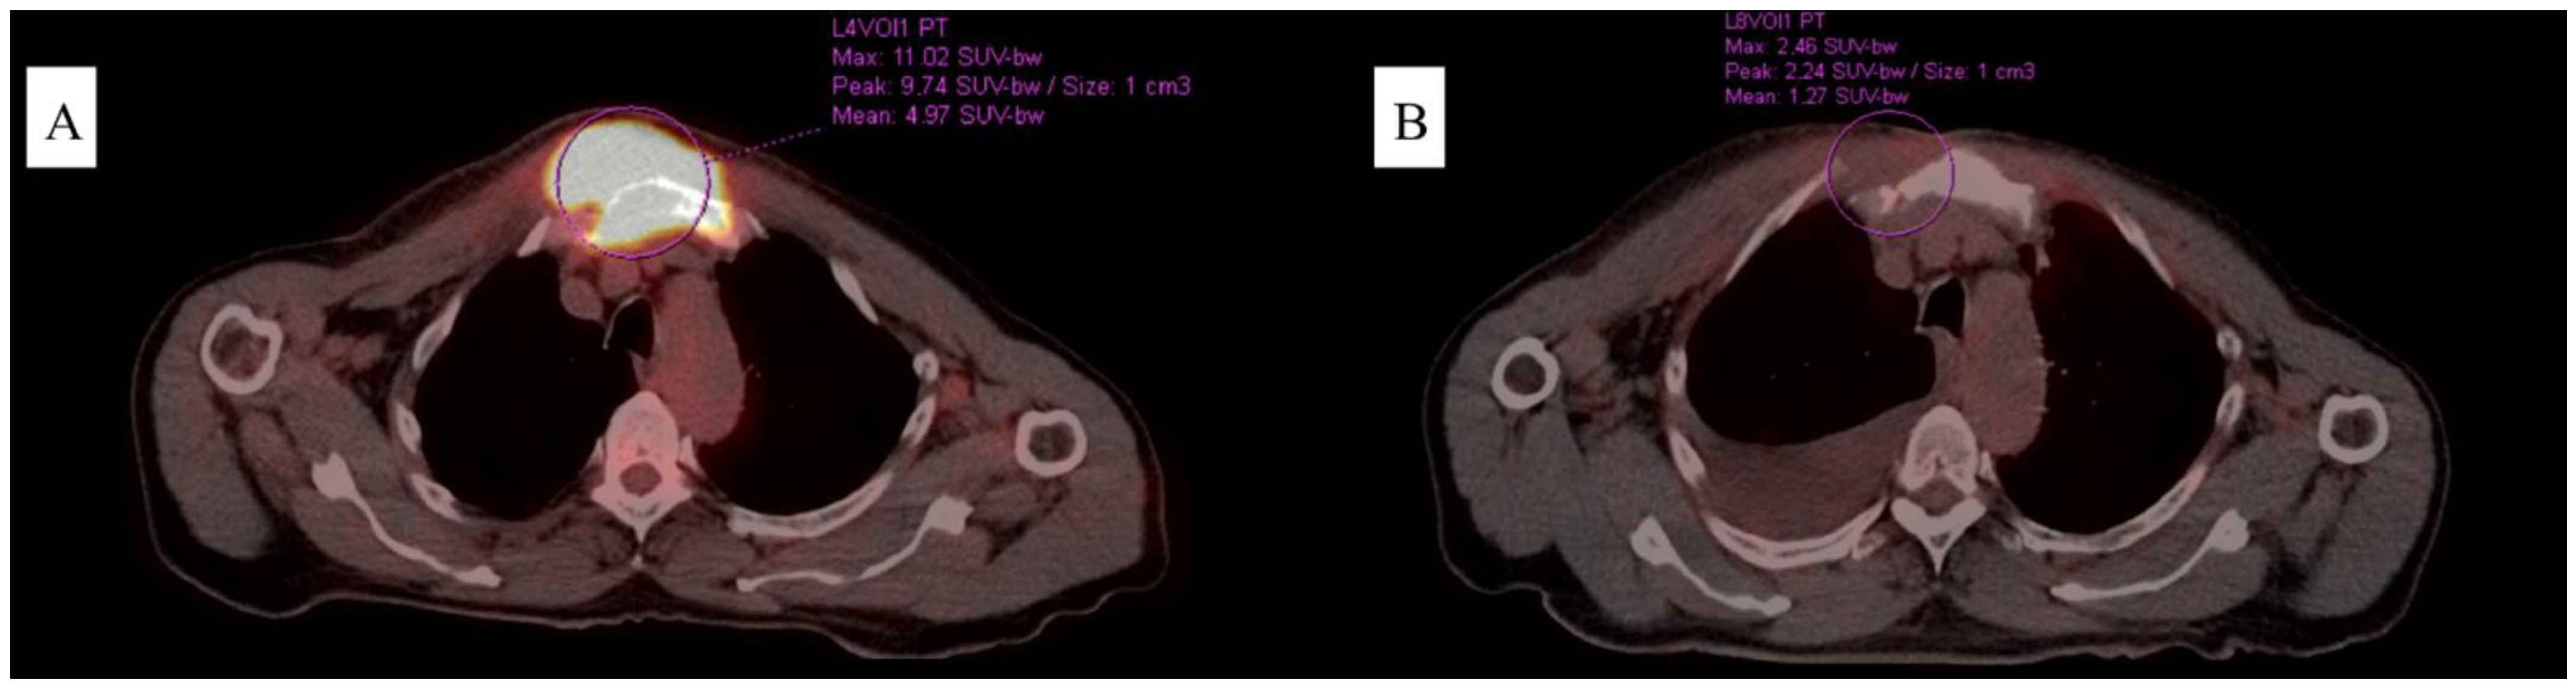

3. Case 1

4. Case 2